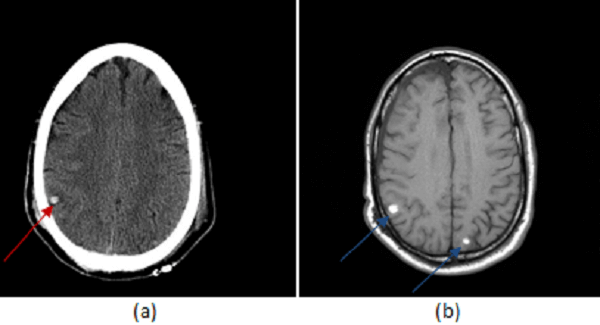

Figure 1: (a, red arrow) non contrast head CT shows a small hemorrhagic contusion in the right parietal lobe. (b, blue arrow) T1 weighted imaging demonstrates two small foci of T1 hyperintense signal consistent with hemorrhage at the grey white junction. (c, green arrow) T2* imaging is most sensitive for blood and intracranial trauma, demonstrating the hemorrhagic contusions identified in (a) and (b) but also a focus of diffuse axonal injury in the left frontal white matter (brown arrow). (Note the hemorrhages are INTRA-axial, not extra-axial as suggested by the answers.)

Initial CT scans may be negative or demonstrate small hemorrhagic contusions. MRI is the gold standard for the evaluation of diffuse axonal injury and demonstrates foci of microscopic hemorrhage in susceptible areas. The appearance of blood on T1 and T2-weighted images depends on its age; these sequences are also less sensitive for the detection of small hemorrhagic foci. As such, susceptibility weighted (SWI) or gradient recalled echo (GRE, T2*) imaging is the preferred method for demonstrating axonal injury. Unlike T1/T2 (spin echo) imaging, SWI and GRE, are sensitive to local inhomogeneity in the magnetic field created by small amounts of blood or calcium – the result is that DAI manifests as a focal loss of signal on SWI or GRE as seen in Figure 1.